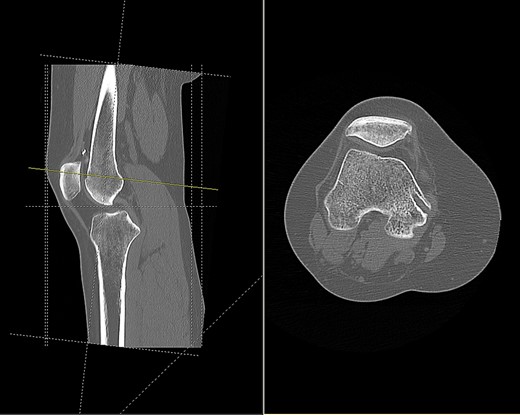

CT scan of the right knee showing perforation of anterior femoral cortex (sagittal and axial view).

Based on tunnel positions, we conclude that the original surgeon had perforated the anterior femoral cortex when drilling from the medial femoral condyle. Due to this an anterior cortex endobutton fixation was used to supplement the medial condylar interference screw fixation. A degree of likely soft tissue interposition in the suprapatellar region led to migration of the endobutton, and subsequent rupture from its scar tissue bed following minimal trauma.